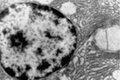

2. Transmission Electron Microscopy Processing unit

1. Transmission Electron Microscope2. Scanning Electron Microscope

1. Transmission Electron Microscope (TEM) processing unit2. Scanning Electron Microscope (SEM) processing unit3. Ultra Microtome and Histopathology4. Experience in the field of specimen preparation for past 16 years